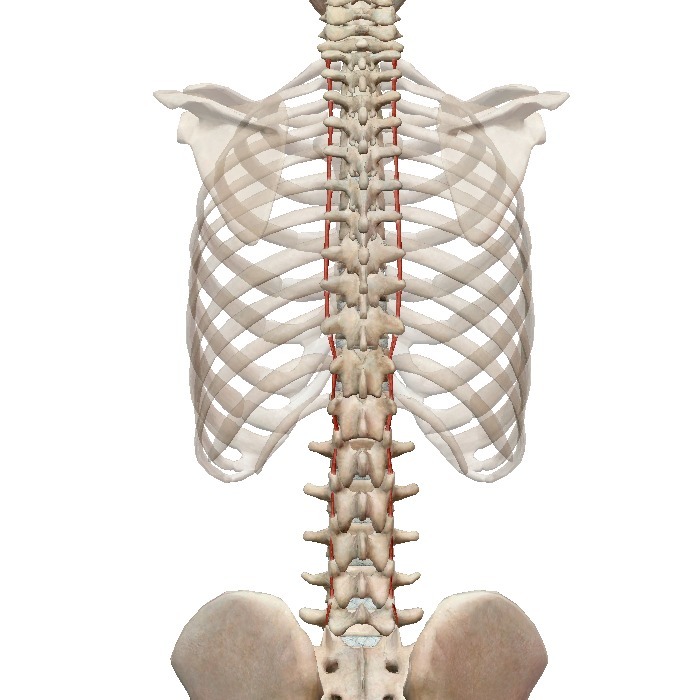

3. Межостистые мышцы,самый глубокий слой. Расположены между остистыми отростками соседних позвонков почти по всей длине позвоночника,кроме крестца и копчика. Функции всё те же -- разгибание и удерживание позвоночника.

4. Межпоперечные мышцы расположены также по всей длине позвоночника кроме крестца и копчика между поперечными отростками позвонков. Удерживают позвоночный столб в вертикальном положении и наклоняют его.

(Картинки даны последовательно)